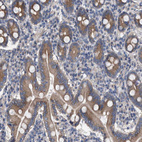

Immunohistochemical staining of human duodenum shows strong cytoplasmic positivity in glandular cells.